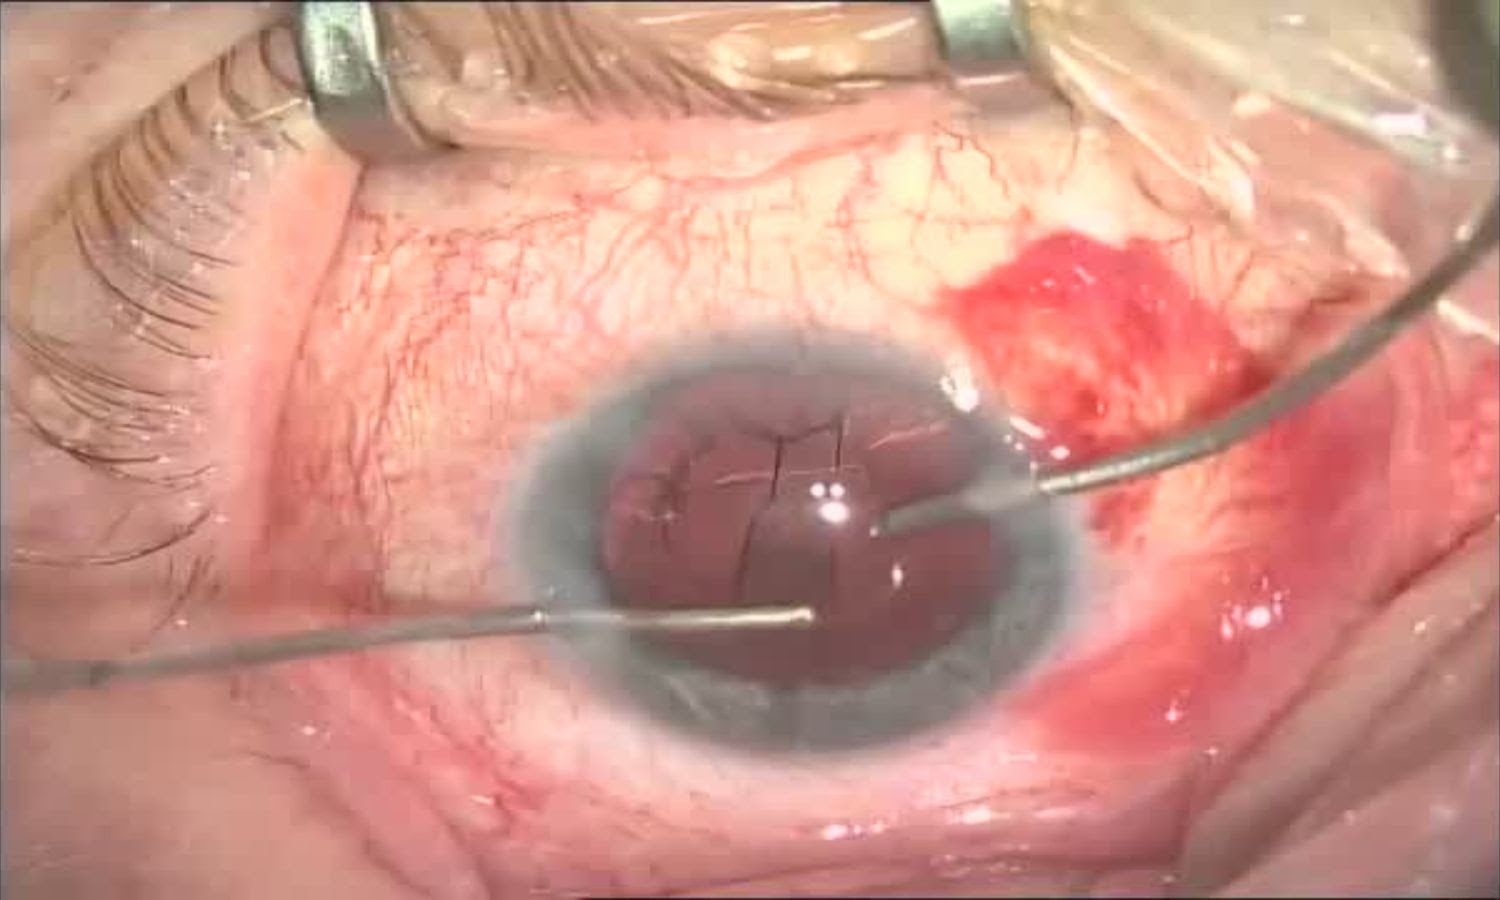

После проделанной работы в глазу остаётся пустое пространство — капсула хрусталика, своего рода «карман», в котором вскоре окажется интраокулярная линза. Если представить себе хрусталик в виде виноградины, то внутреннее содержимое удаляется и остаётся прозрачная оболочка с отверстием на передней стенке.

Обратите внимание на две фотографии: они отличаются тем, что на первой зрачок красный, а на второй — чёрный. В первом случае на хрусталике ещё присутствует красный свет — по сути, это рефлекс с глазного дна с кровеносными сосудами. Во втором случае хрусталика уже нет и наклон коаксиального осветителя другой — без линзы рефракция меняется и дна мы уже не видим — только саму «дырку» в глазу. Тьма, бездна )

Введение вискоэластика и расправления капсульного мешка перед имплантацией